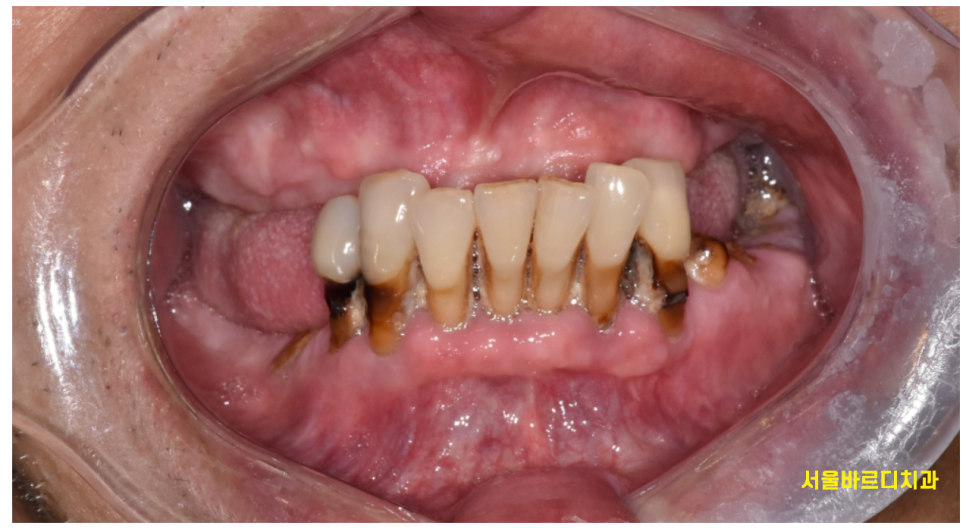

고덕역 치과를 찾아오신 a 할아버지

10년동안 틀니를 쓰셨답니다.

이젠 잘 맞지도 않고

치과에는 이골이 나서 한동안 발길을 끊으셨답니다.

231109

아래 어금니는 빠진채로

그냥 방치해두셨다는데요.

그나마 남아 있는 앞니는 충치로 가득